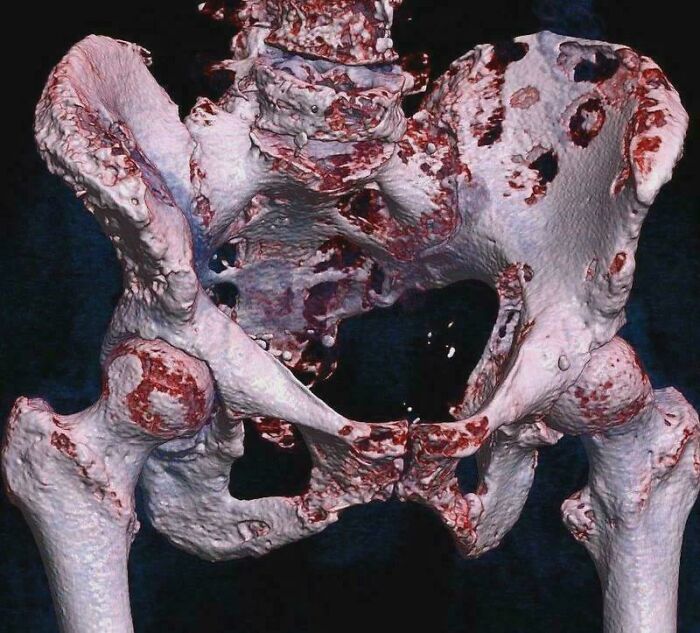

#32 This Photo Shows A 3D Rendered CT Scan Of Bone Metastases Of The Hip Bone, In A 60-Year-Old Woman With Parotid Gland Cancer

Large lesions are seen on the ilium on the more distant side. Involvement of the vertebral column has caused a compression fracture.

Image source: GiorgioMD